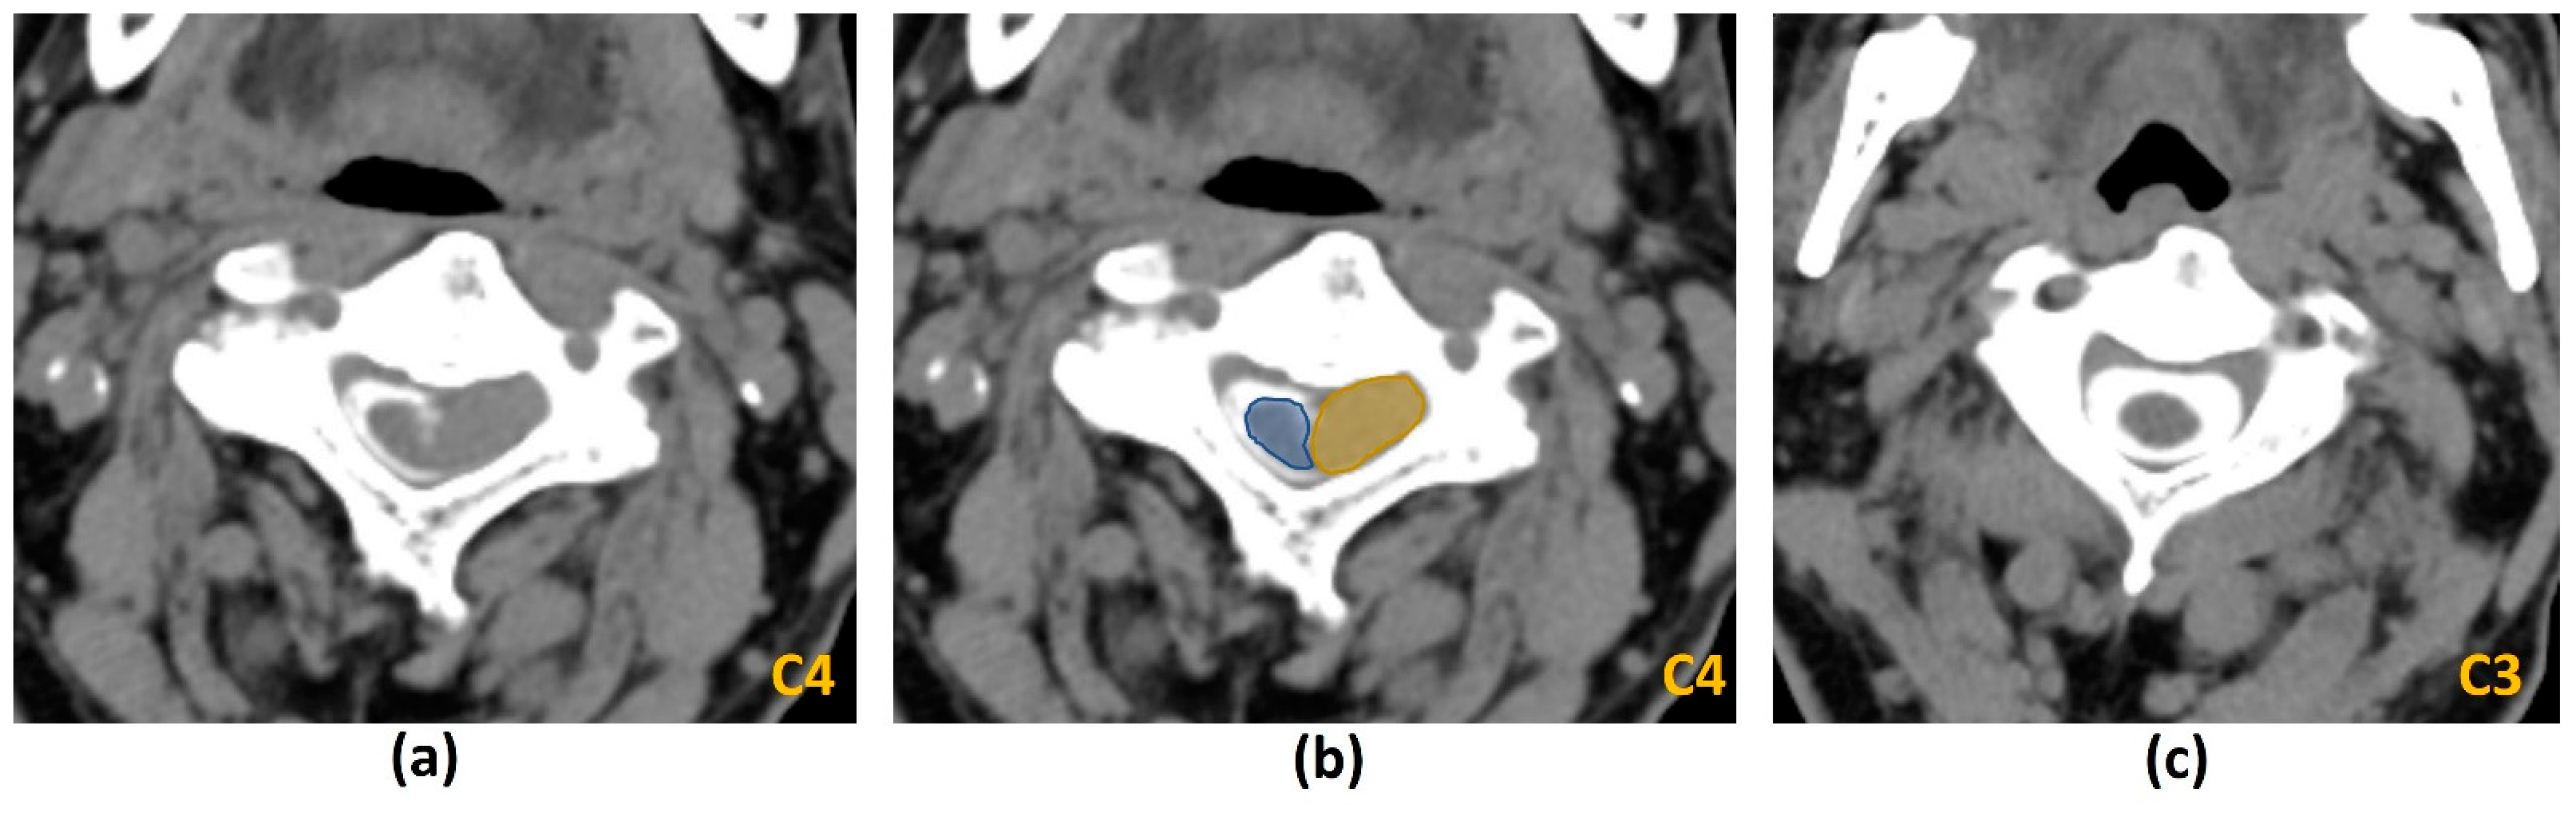

- Krätzig, T.; Mende, K.C.; Mohme, M.; Kniep, H.; Dreimann, M.; Stangenberg, M.; Westphal, M.; Gauer, T.; Eicker, S.O. Carbon fiber-reinforced PEEK versus titanium implants: An in vitro comparison of susceptibility artifacts in CT and MR imaging. Neurosurg. Rev. 2021, 44, 2163–2170. [Google Scholar] [CrossRef]

- Kumar, N.; Lopez, K.G.; Alathur Ramakrishnan, S.; Hallinan, J.T.P.D.; Fuh, J.Y.H.; Pandita, N.; Madhu, S.; Kumar, A.; Benneker, L.M.; Vellayappan, B.A. Evolution of materials for implants in metastatic spine disease till date—Have we found an ideal material? Radiother Oncol. 2021, 163, 93–104. [Google Scholar] [CrossRef] [PubMed]

- Kumar, N.; Ramakrishnan, S.A.; Lopez, K.G.; Madhu, S.; Ramos, M.R.D.; Fuh, J.Y.H.; Hallinan, J.; Nolan, C.P.; Benneker, L.M.; Vellayappan, B.A. Can Polyether Ether Ketone Dethrone Titanium as the Choice Implant Material for Metastatic Spine Tumor Surgery? World Neurosurg. 2021, 148, 94–109. [Google Scholar] [CrossRef] [PubMed]

- Zimel, M.N.; Hwang, S.; Riedel, E.R.; Healey, J.H. Carbon fiber intramedullary nails reduce artifact in postoperative advanced imaging. Skelet. Radiol. 2015, 44, 1317–1325. [Google Scholar] [CrossRef]

- Osterhoff, G.; Huber, F.A.; Graf, L.C.; Erdlen, F.; Pape, H.C.; Sprengel, K.; Guggenberger, R. Comparison of metal artifact reduction techniques in magnetic resonance imaging of carbon-reinforced PEEK and titanium spinal implants. Acta Radiol. 2021, 2841851211029077. [Google Scholar] [CrossRef]

- Katsura, M.; Sato, J.; Akahane, M.; Kunimatsu, A.; Abe, O. Current and Novel Techniques for Metal Artifact Reduction at CT: Practical Guide for Radiologists. Radiographics 2018, 38, 450–461. [Google Scholar] [CrossRef] [PubMed] [Green Version]

- Huber, F.A.; Sprengel, K.; Müller, L.; Graf, L.C.; Osterhoff, G.; Guggenberger, R. Comparison of different CT metal artifact reduction strategies for standard titanium and carbon-fiber reinforced polymer implants in sheep cadavers. BMC Med. Imaging 2021, 21, 29. [Google Scholar] [CrossRef]